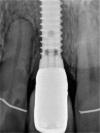

Introduction: Dental implants have become a standard treatment in the replacement of missing teeth. After tooth extraction and implant placement, resorption of buccal bundle bone can pose a significant complication with often very negative cosmetic impacts. Studies have shown that if the dental root remains in the alveolar process, bundle bone resorption is very minimal. However, to date, the deliberate retention of roots to preserve bone has not been routinely used in dental implantology.

Conclusion: Whilst the socket-shield technique potentially offers promising outcomes, reducing the need for invasive bone grafts around implants in the aesthetic zone, clinical data to support this is very limited. The limited data available is compromised by a lack of well-designed prospective randomised controlled studies. The existing case reports are of very limited scientific value. Retrospective studies exist in limited numbers but are of inconsistent design. At this stage, it is unclear whether the socket-shield technique will provide a stable long-time outcome.